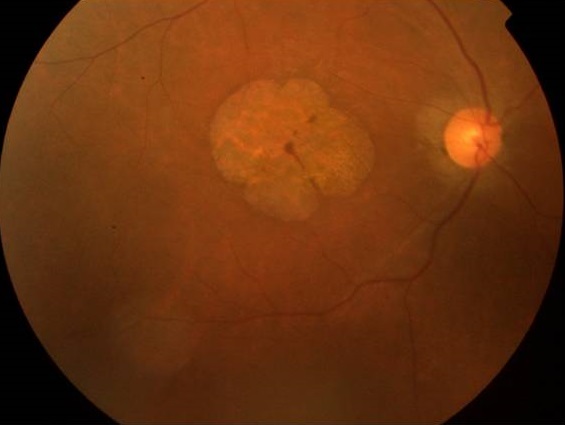

Ataxie spino-cérébelleuse de type 7 (SCA) dignostiqué par l’aspect du fond d’œil

Les ataxies spinocérébelleuses constituent un groupe de maladies neurodégénératives très hétérogènes tant du point de vue clinique que génétique, d'évolution lente et progressive. L'ataxie spino-cérébelleuse de type 7 (SCA7) est un type d'ataxie associé à une dégénérescence rétinienne. Nous présentons un cas familial de SCA7 avec maculopathie atrophique bilatérale. Il s'agit d'un patient âgé de 24 ans présentant depuis l'adolescence une baisse de l'acuité visuelle progressive associée à une ataxie et une dysarthrie. L'interrogatoire a permis de déceler la présence de deux cas similaires dans sa famille. A l'examen, on trouve au niveau des deux yeux :une AV réduite au décompte les doigts de près, un segment antérieur normal et au FO une aire d'atrophie maculaire circulaire. L'ERG global et P-ERG ont montré des réponses altérées des deux systèmes photopique et scotopique.L'examen de la vision colorée a montré une dyschromatopsie sans axe précis. L'examen neurologique et la neuro-imagerie étaient en faveur d'une affection hérédo-dégénérative type SCA7. La SCA7 appartient aux ataxiescérébelleusesautosomiques dominantesde type II (ACAD II), selon la classification de Harding. Elle se caractérise par une ataxie cérébelleuse progressiveet et une dystrophie rétinienne progressive notamment maculaire, avec perte de la vision centrale entraînant la cécité chez les adultes touchés. L'atteinte rétinienne permet de classer cette forme clinique. Le bilan électrophysiologique demandé devant la baisse d'acuité visuelle permet de préciser le type de dysfonctionnement rétinien, tel qu'il a été le cas chez notre patient. L'examen ophtalmologique avec électrophysiologie rétinienne et l'examen neurologique avec exploration neuroradiologique permettent de poser le diagnostic.